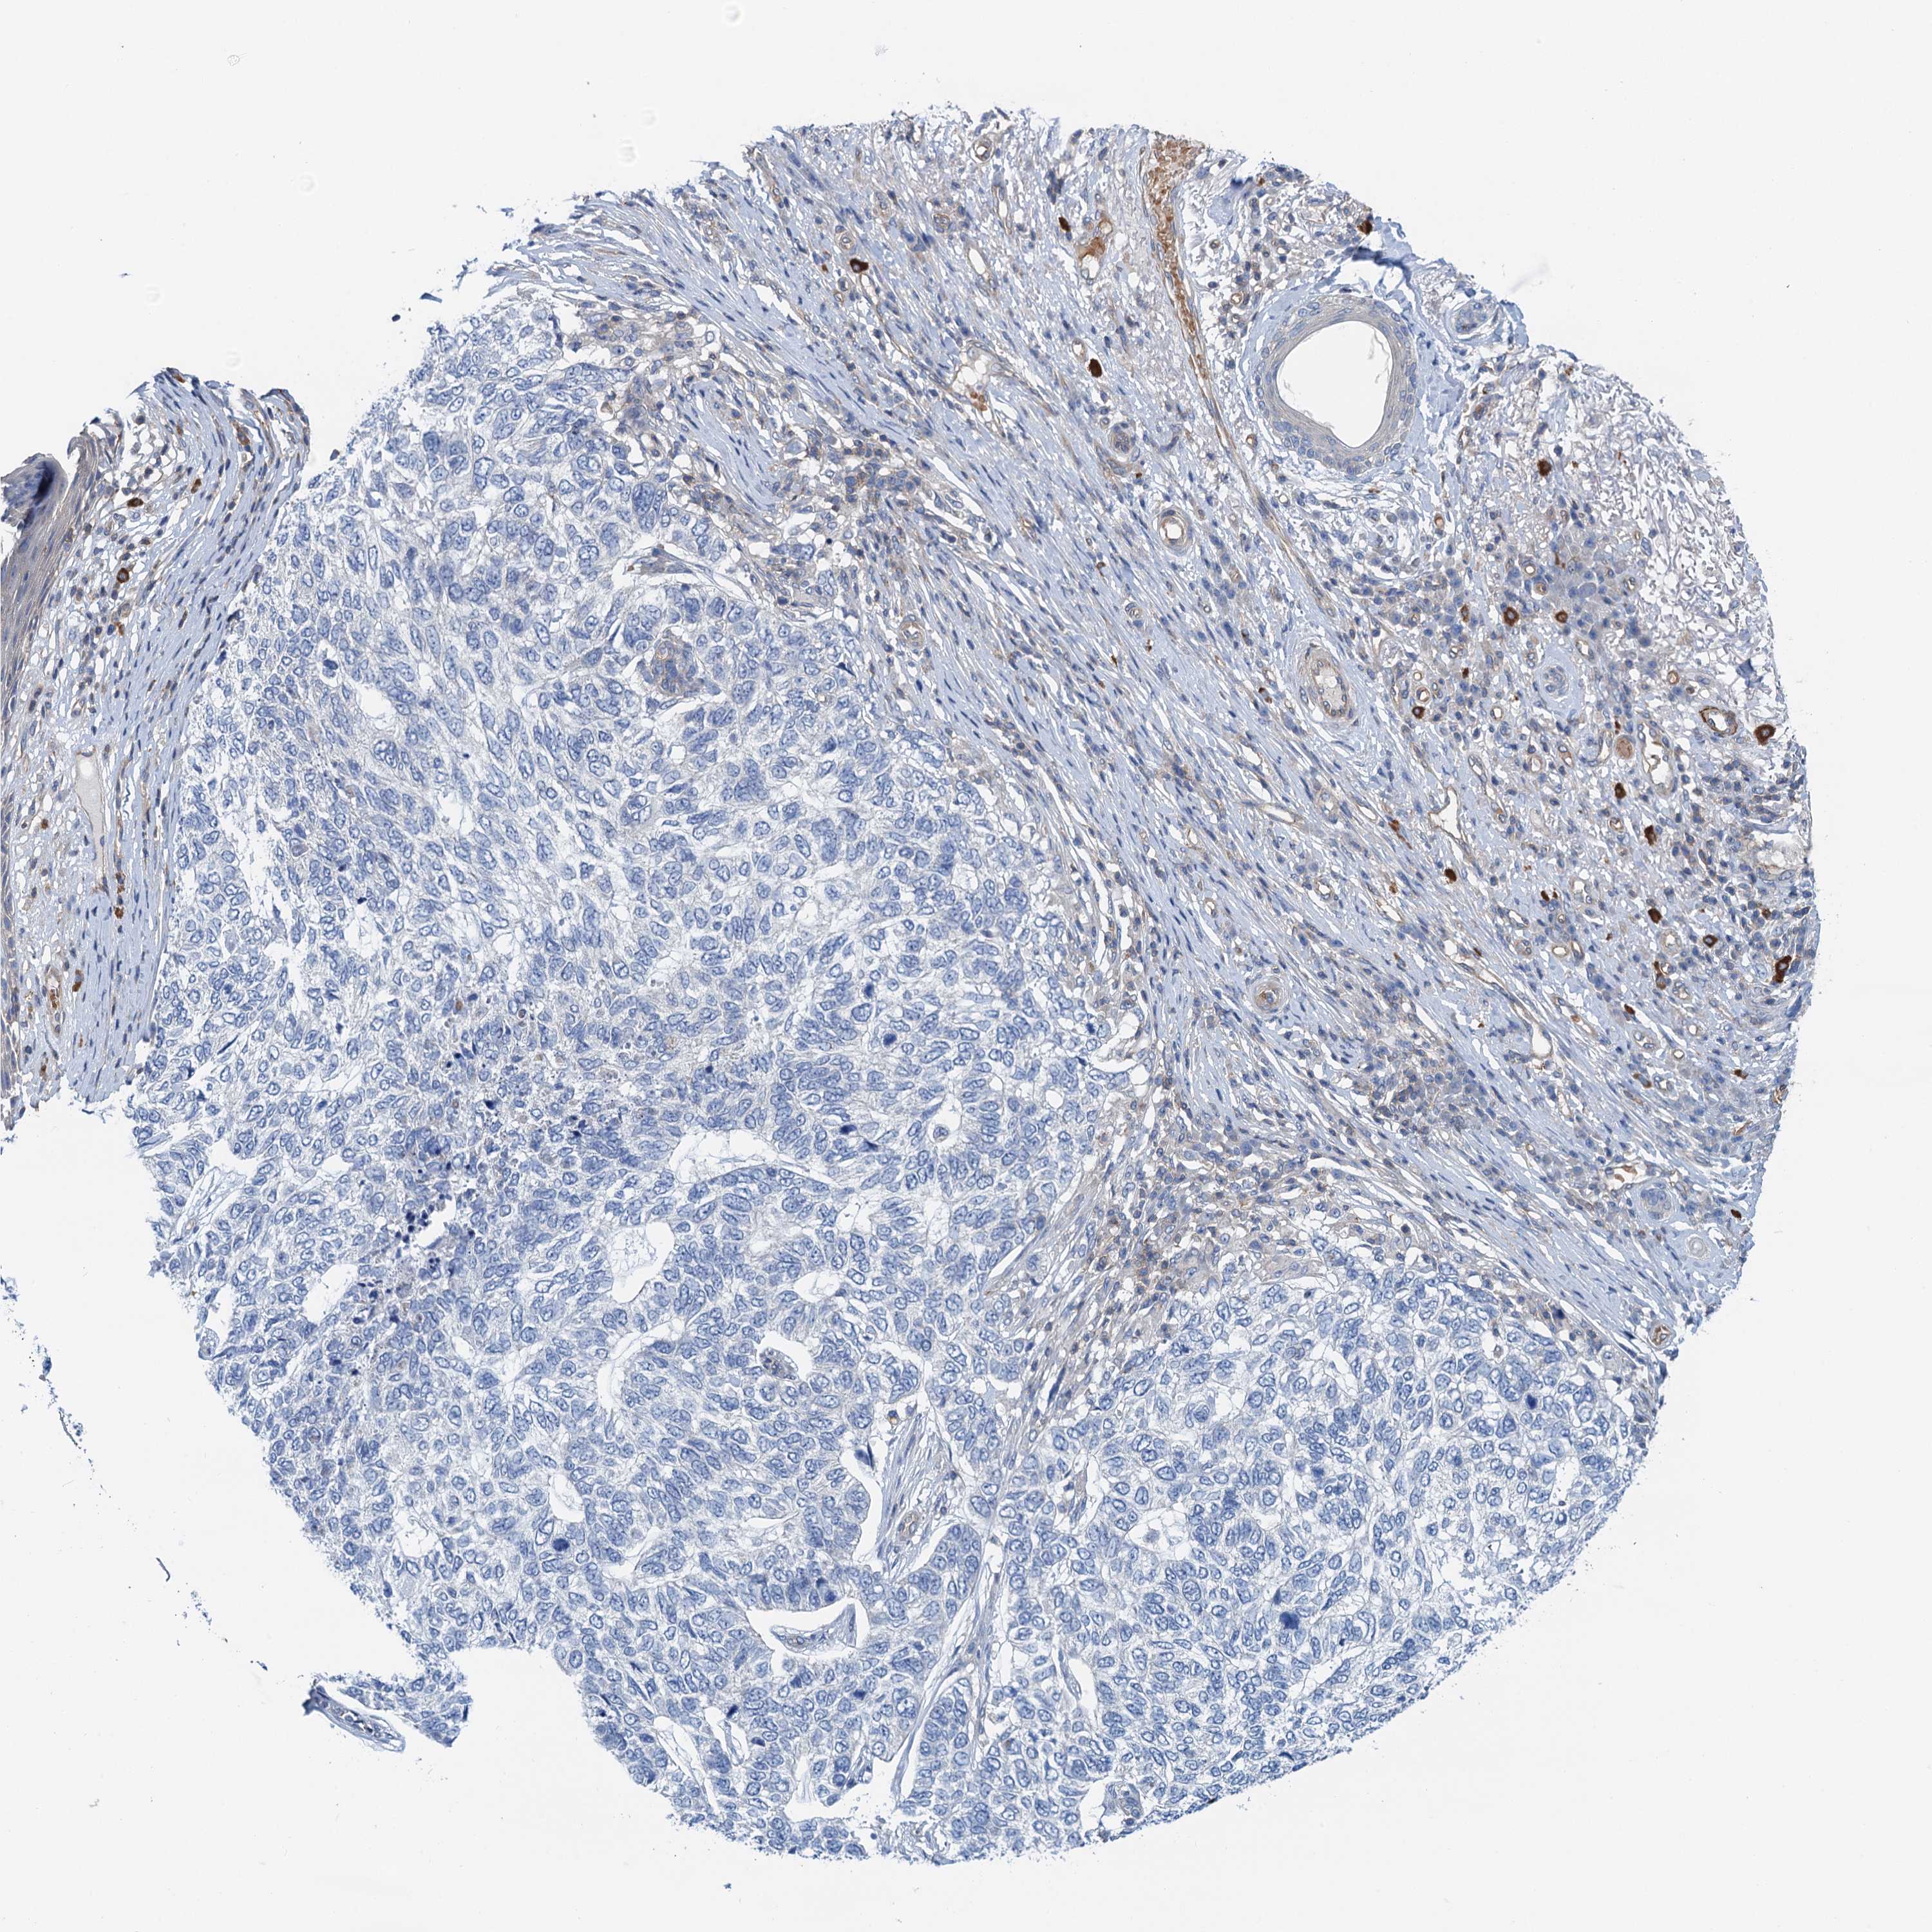

SKIN CANCER - Protein expressioni

A mouse-over function shows sample information and annotation data. Click on an image to view it in a full screen mode. Samples can be filtered based on level of antibody staining by selecting one or several of the following categories: high, medium, low and not detected. The assay and annotation is described here.

Each image is clickable and will lead to virtual microscopy that enables deeper exploration of all samples and also displays staining intensity scores, fraction scores and subcellular localization as well as patient and tissue information for each sample.

Antibody HPA041000

Staining

High

Medium

Low

Not detected

Intensity

Strong

Moderate

Weak

Negative

Quantity

>75%

75%-25%

<25%

None

Location

Nuclear

Cytoplasmic/membranous

Cytoplasmic/membranous,nuclear

Basal cell carcinoma